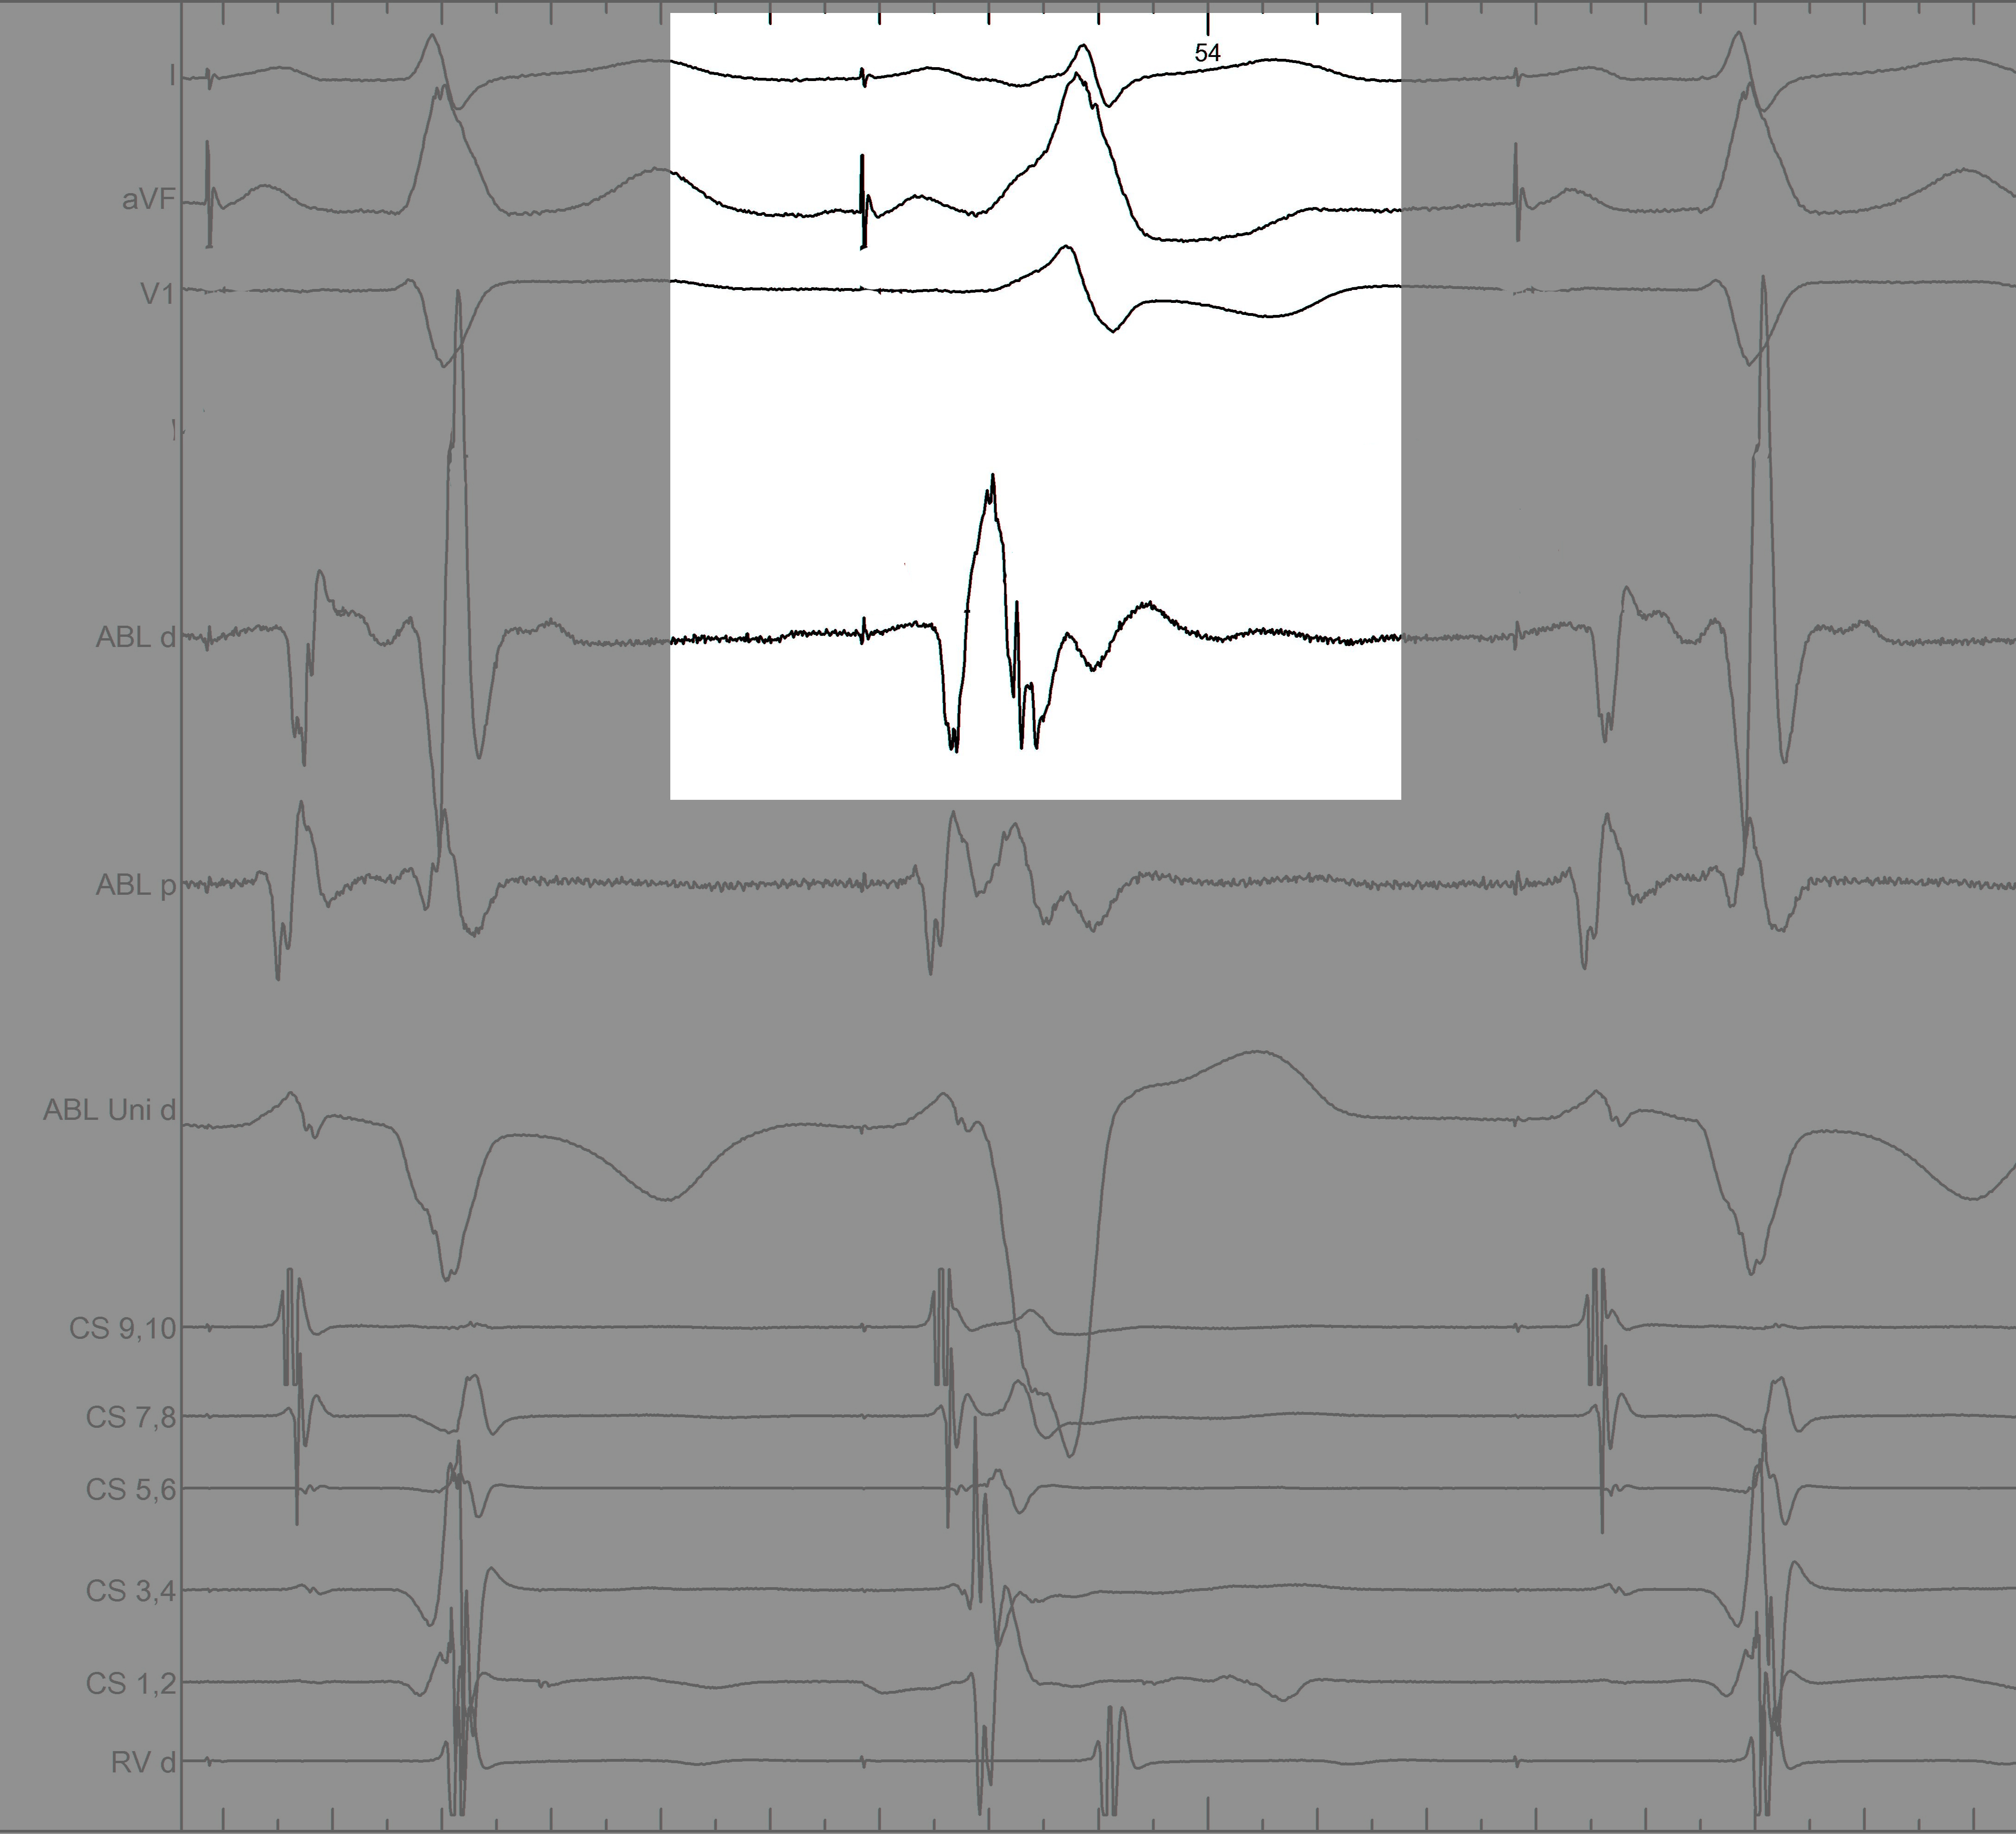

mask1.jpg

Information from other electrodes

mask2.jpg

Unipolar

mask3.jpg

Non preexcited beats

mask4.jpg